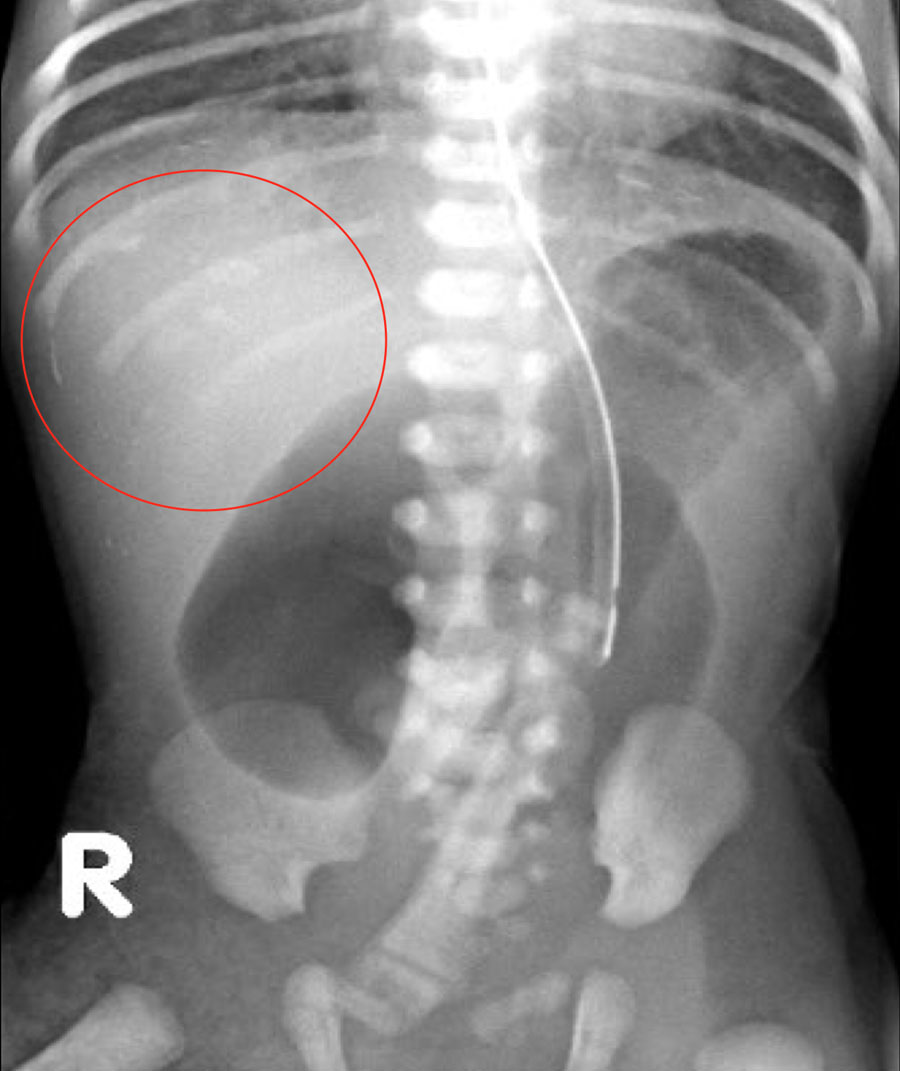

Trên hình ảnh bên trái, ruột bị giãn và đường kính vượt quá khoảng cách liên cuống L2 ở bệnh nhân tắc ruột phân su.

Hình ảnh cho thấy một trẻ sơ sinh với các quai ruột giãn.

Không có khí trong trực tràng.

Bệnh nhân này bị tắc ruột phân su.